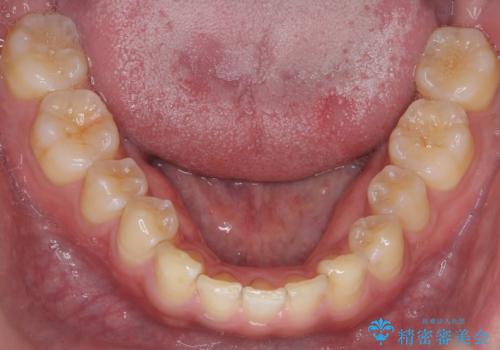

前歯のすき間 小さい歯がある 前歯の並びをきれいにしたい

- 前歯のすき間を気にして来院。

前から2番目の歯が小さく厚みがあったため(矮小歯)

矯正治療で1番目の歯を寄せて2番目の歯はセラミックで形をととのえています。